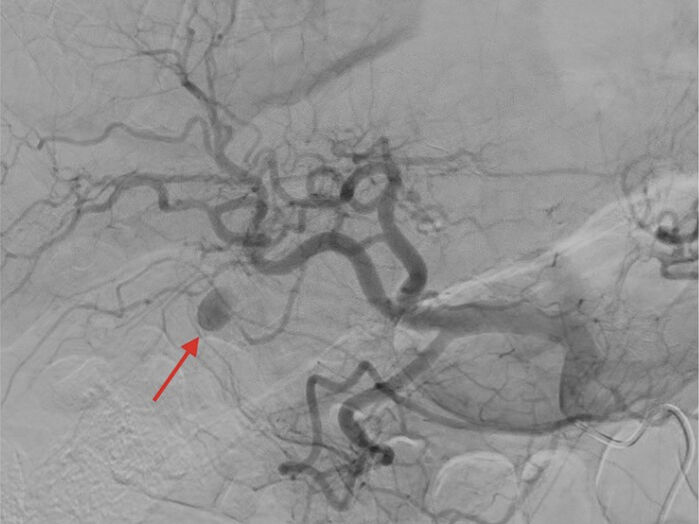

Klínískt ástand hélst óbreytt næstu þrjá daga þar til kviðverkirnir versnuðu til muna og þensla á kvið jókst. Ný tölvusneiðmynd sýndi að gallsteinn, sem áður hafði verið í gallblöðru, var í fjærenda dausgarnar (ileum) og olli garnastíflu (mynd 1).

Mynd 1. Tölvusneiðmyndir A sýna að gallsteinn (ör) er í gallblöðru. B sýna að steinninn (ör) er kominn neðarlega í smágirni í hæð við mjaðmagrind. Myndirnar eru teknar með þriggja daga millibili.